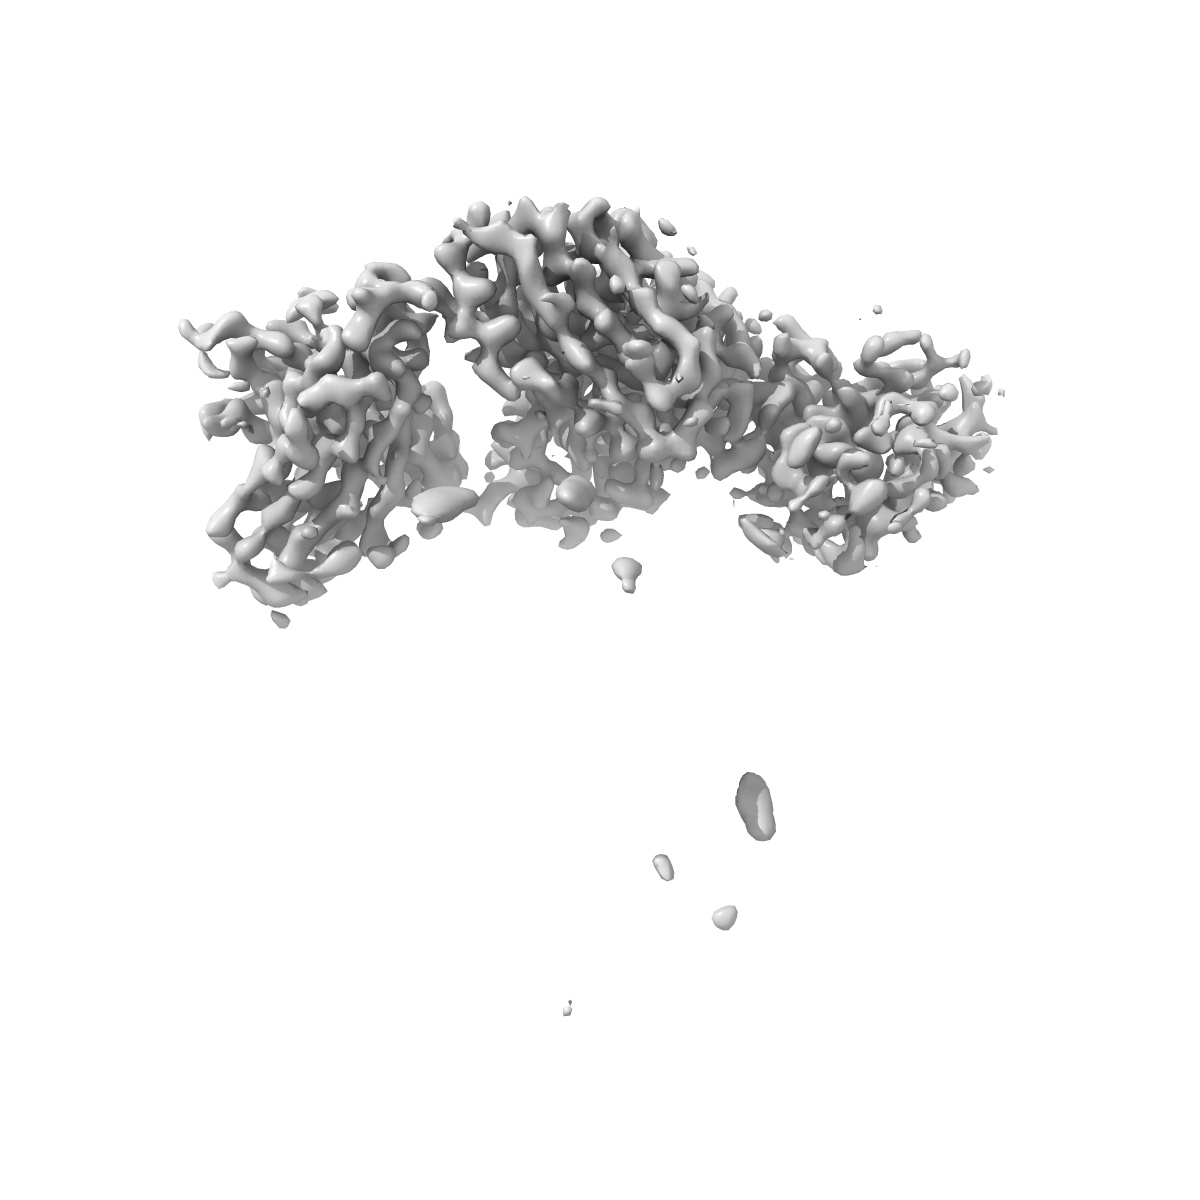

Cryo-EM structure of human monoclonal antibody C74 targeting IT4VAR22 CIDRa1.7

Single-particle3.35 Å

Sample: Plasmodium falciparum Erythrocyte Membrane Protein 1 in complex with human monoclonal antibody

Fitted models: 8vdg

Broadly inhibitory antibodies to severe malaria virulence proteins.